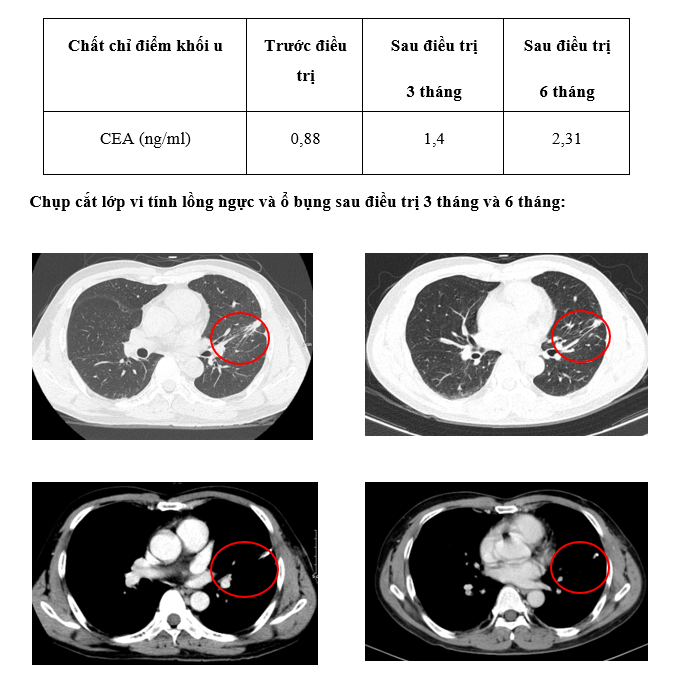

Xét nghiệm chất chỉ điểm u: Nồng độ CEA nằm trong giới hạn bình thuờng, ổn định qua các đợt điều trị:

Lâm sàng: Sau 3 tháng bệnh nhân không còn đau tức ngực, không ho, không khó thở. Sau 6 tháng bệnh nhân ổn định, tăng cân, đại tiểu tiện bình thường, không đau ngực, không khó thở.

– Bệnh nhân được điều trị hóa chất phác đồ XELOX kết hợp thuốc đích kháng sinh mạch Bevacizumab x 4 chu kỳ -> sau đó phẫu thuật cắt một phần thùy trên phổi trái chứa u. Sau phẫu thuật, điều trị 4 chu kỳ XELOX + Bevacizumab